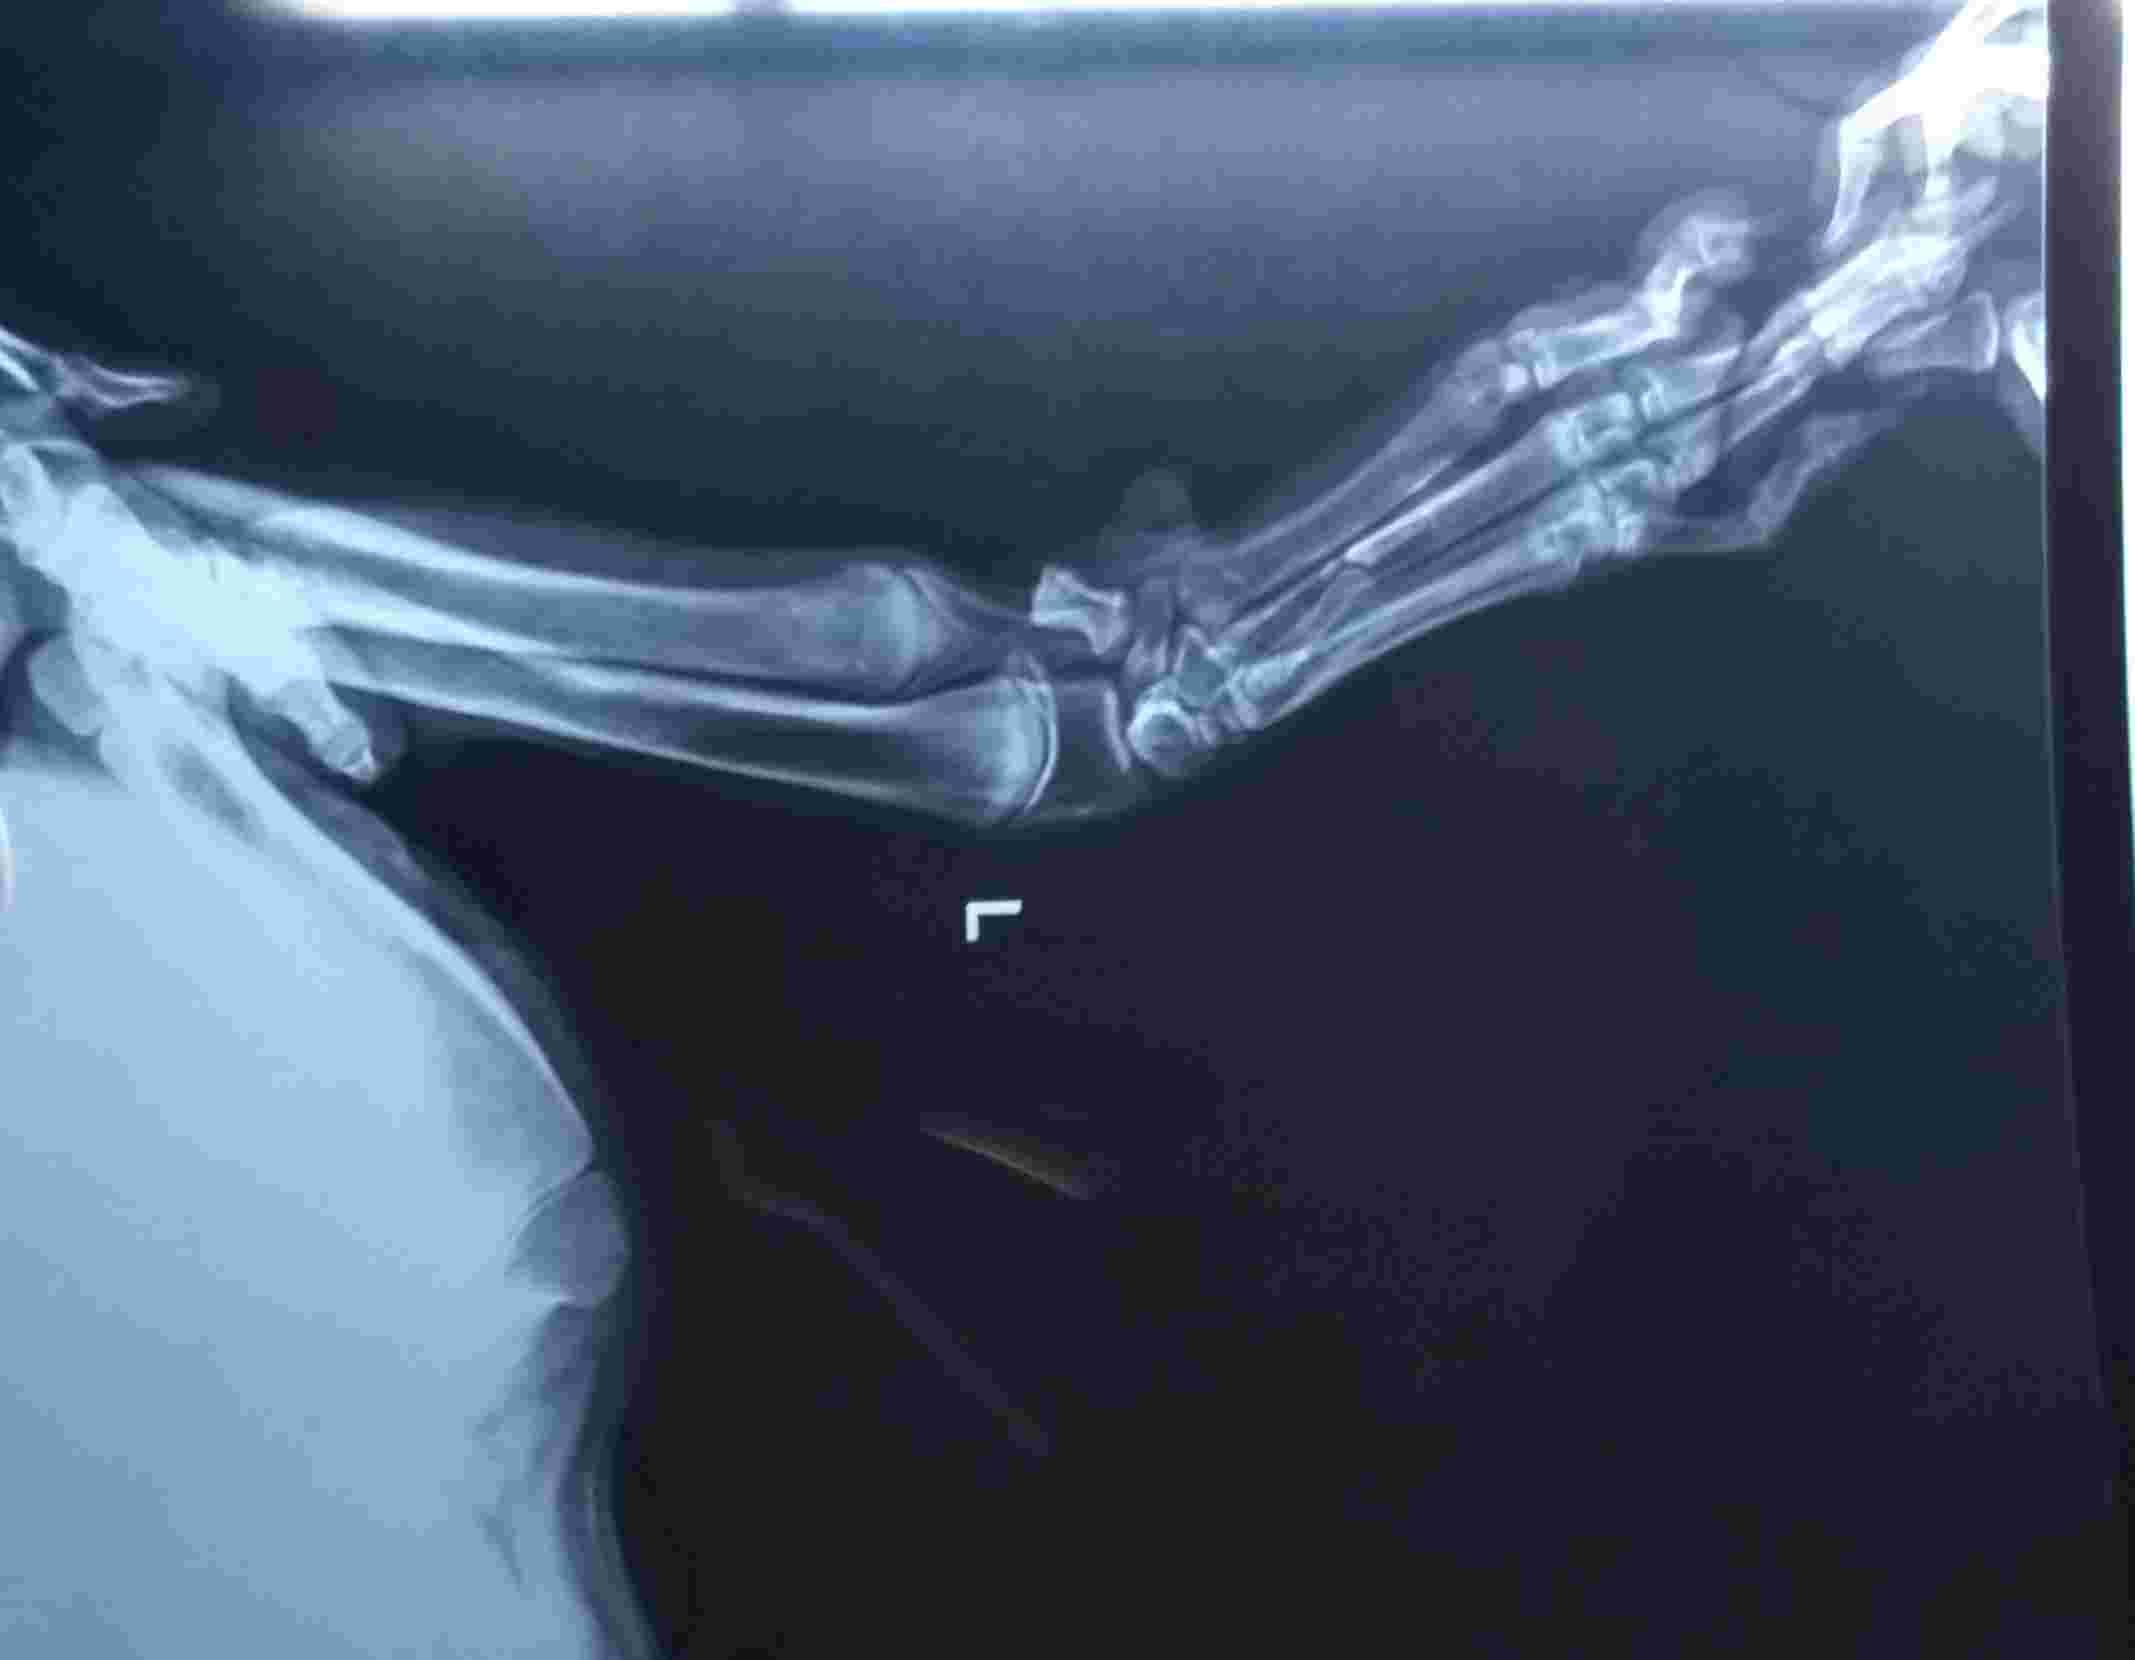

My dog has carpal valgus. Will he get arthritis or joint issues?

Like by looking attach xray report you said he has carpal valgas deformity so will his life span going to affect ? Will he going to have arthritis or any other problem related to this carpal valgas deformity later in life or in coming days ?

At his age, Danny is likely done growing. Having a valgas deformity will predispose him to developing arthritis or other joint issues later in life, but should not affect his lifespan. There are treatment options you can discuss with your veterinarian or a veterinary orthopedic specialist.